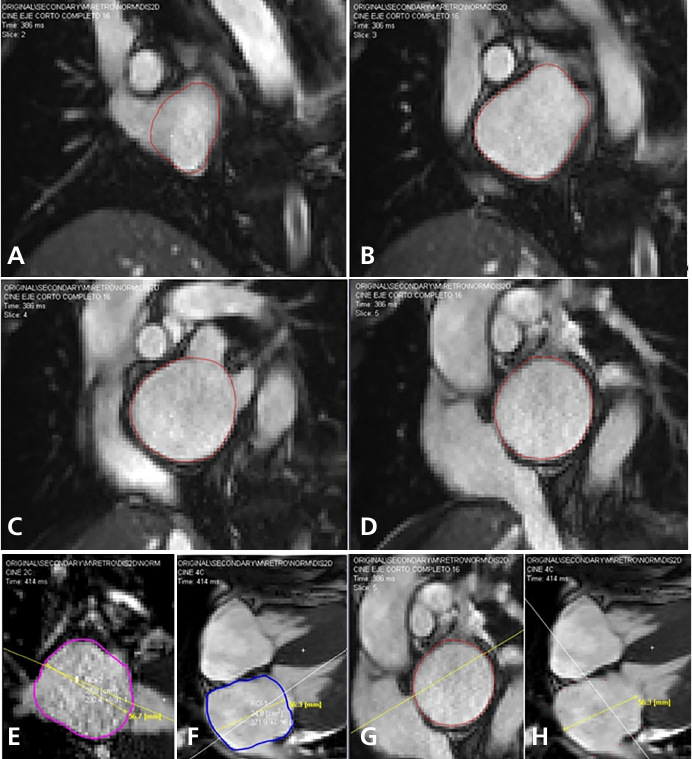

Figure 1 shows images of direct LA volume measurement using the AL and CBI methods.

Left atrial measurements performed in the complete short-axis, 4C, and 2C views with manual endocardial tracing at end-systole. Direct volumetry (A-B-C-D). AL method (E-F). CBI method (G-H)